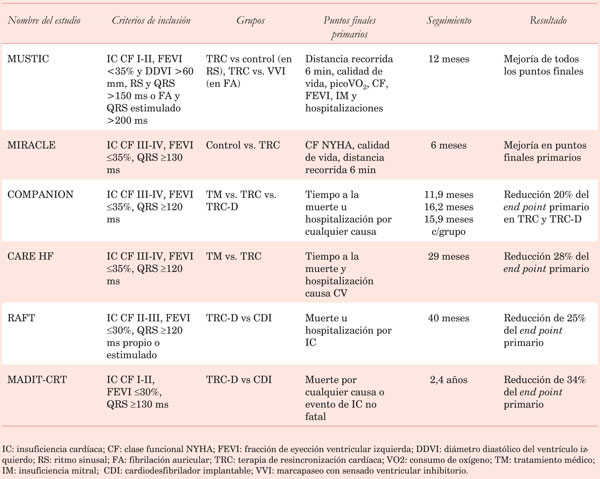

La TRC se aplica clínicamente desde hace más de 20 años. Ha sido demostrada su eficacia en múltiples estudios randomizados y multicéntricos en pacientes con IC CF II-IV, FEVI <35% y BCRI. El primer estudio con estas características fue el MUSTIC23 publicado en 2001. Le siguió el estudio MIRACLE24, con una mayor cantidad de pacientes. En ambos se demostró una mejoría significativa en los síntomas, pero no disminución de la mortalidad total.

El estudio COMPANION14 fue el primero que agregó la terapia de desfibrilación a la TRC, demostrando beneficio en la disminución de la mortalidad con la TRC más el CDI (TRC-D)24. Sin embargo, fue el estudio CARE-HF el que demostró una consistente reducción de la mortalidad de la TRC en ausencia de desfibrilador (TRC-P) (Figura 2)25.

Figura 2: Curvas de Kaplan-Meier del estudio CARE-HF para tiempo al end point primario (A) y secundario (B). Modificado de referencia 24.

El estudio RAFT26 fue de los pocos que comparó TRC-D con terapia con CDI solo en pacientes con FEVI <30%, CF II-III y duración del QRS >120 ms. Mostró una disminución absoluta de 7% de la mortalidad total u hospitalización por IC con TRC-D.

El estudio MADIT-CRT27 randomizó pacientes con IC CF I-II, FEVI <30% y duración del QRS >130 ms a TRC-D y a desfibrilador solo. Mostró una reducción del punto final combinado de mortalidad y descompensación de IC, sugiriendo que los pacientes en estadios precoces de IC también se benefician de la TRC. Este concepto fue reafirmado en el estudio REVERSE28, que mostró beneficio en los síntomas con la TRC en pacientes con IC CF I-II.

La (Tabla 2) muestra las características de los estudios más importantes, los criterios de inclusión, los puntos finales y sus resultados.